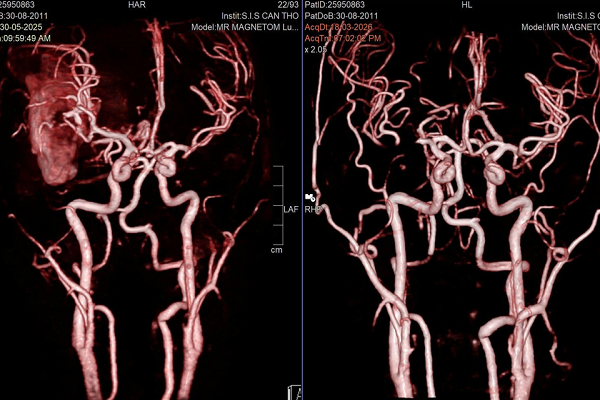

Bệnh nhân bị xuất huyết não do vỡ dị dạng mạch máu não (AVM – Arteriovenous Malformation)

Tại đây, các bác sĩ nhanh chóng xác định nguyên nhân: xuất huyết não do vỡ dị dạng mạch máu não (AVM – Arteriovenous Malformation). Đây là một bệnh lý bẩm sinh, trong đó các động mạch và tĩnh mạch kết nối bất thường, tạo ra áp lực lớn lên thành mạch và có thể vỡ bất cứ lúc nào.

Đầu tiên, bệnh nhân được can thiệp nội mạch nhằm giảm lưu lượng máu đến ổ dị dạng, hạn chế nguy cơ chảy máu tiếp diễn. Ngay sau đó, các bác sĩ tiến hành phẫu thuật mở sọ, bóc tách và loại bỏ toàn bộ búi dị dạng cùng khối máu tụ.